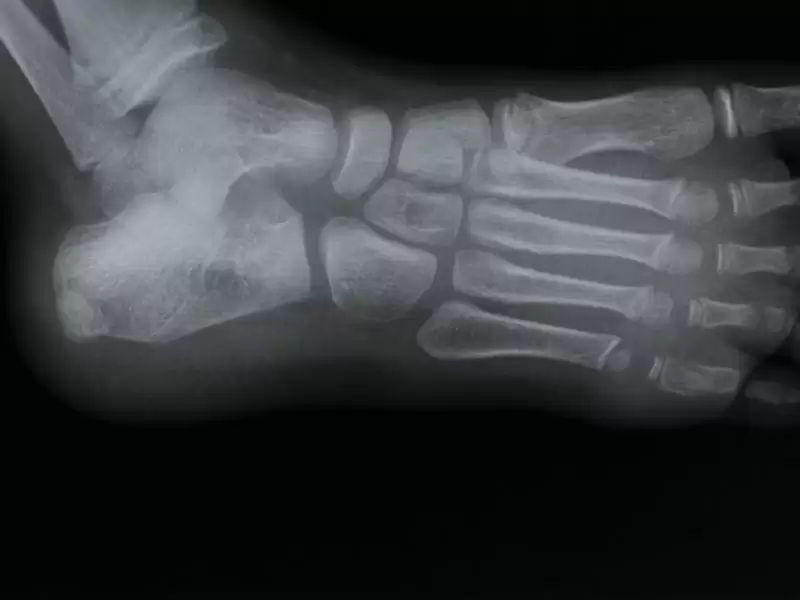

Ayak ve Ön Ayak Kırıkları

Hemen hemen hareket ve desteği sağlayan vücut kemiklerinin dörtte biri ayaklardadır. Ön ayağınızdaki (metatars) veya aya...

Talus Kırığı

Talus kırığı; ayak bileğinde görülen ciddi ortopedik bir problemdir. Ayak ve ayak bileği anatomisi oldukça karmaşık, bir...